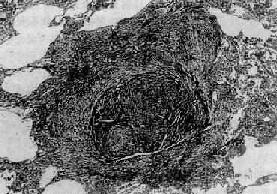

矽肺的基本病变是肺组织内矽结节形成和弥漫性间质纤维化。矽结节是矽肺的特征性病变,结节境界清楚,直径2~5mm,呈圆形或椭圆形,灰白色,质硬,触之有砂样感。随着病变的发展,结节可融合成团块状,在团块的中央,由于缺血、缺氧而发生坏死、液化,形成矽肺性空洞(silicotic cavity)。矽结节的形成过程大致分为三个阶段:①细胞性结节,由吞噬矽尘的巨噬结胞局灶性聚积而成,巨噬细胞间有网状纤维,这是早期的矽结节;②纤维性结节,由纤维母细胞、纤维细胞和胶原纤维构成;③玻璃样结节,玻璃样变从结节中央开始,逐渐向周围发展,往往在发生玻璃样变的结节周围又有新的纤维组织包绕。镜下,典型的矽结节是由呈同心圆状或旋涡状排列的、已发生玻璃样变的胶原纤维构成(图9-22)。结节中央往往可见内膜增厚的血管。用偏光显微镜观察,可以发现沉积在矽结节和肺组织内呈双屈光性的矽尘微粒。除矽结节外,肺内还有不同程度的弥漫性间质纤维化(图9-23),范围可达全肺2/3以上。此外,胸膜也因纤维组织弥漫增生而广泛增厚,在胸壁上也可形成胸膜胼胝,甚至可厚达1~2cm。肺门淋巴结内也有矽结节形成和弥漫性纤维化及钙化,淋巴结因而肿大、变硬。

图9-22 矽肺

矽结节,由呈旋涡状排列的已发生玻璃样变的胶原纤维构成